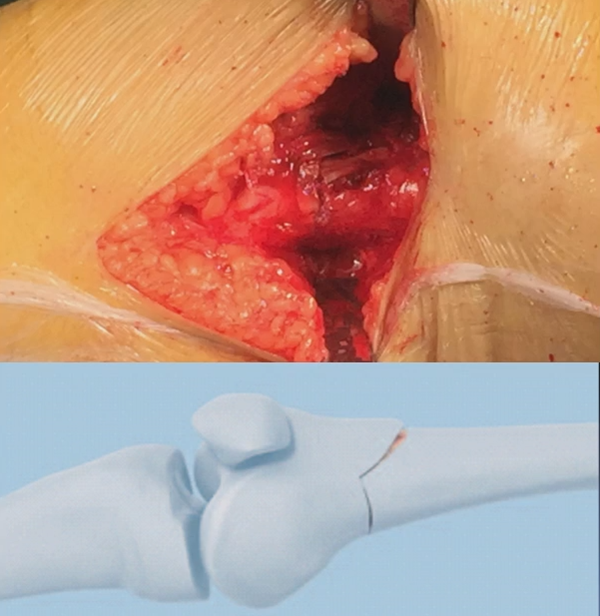

注意,目前临床推荐的DFO要求最好能做双平面截骨,即还要有一条上行截骨线,上行截骨线与水平截骨线夹角大概为95° 左右。这种截骨方式一方面可以增加稳定性,同时也可以减少对上方髌股关节的干扰。

上行截骨时,要保持肢体旋转中立位,前方要有骨撬保护,由内向外完全截开,上行截骨线不存在合页。

处理完后,紧密闭合截骨端。

然后核实力线,如力线位置良好,就可以采用内固定的方式将位置维持好。